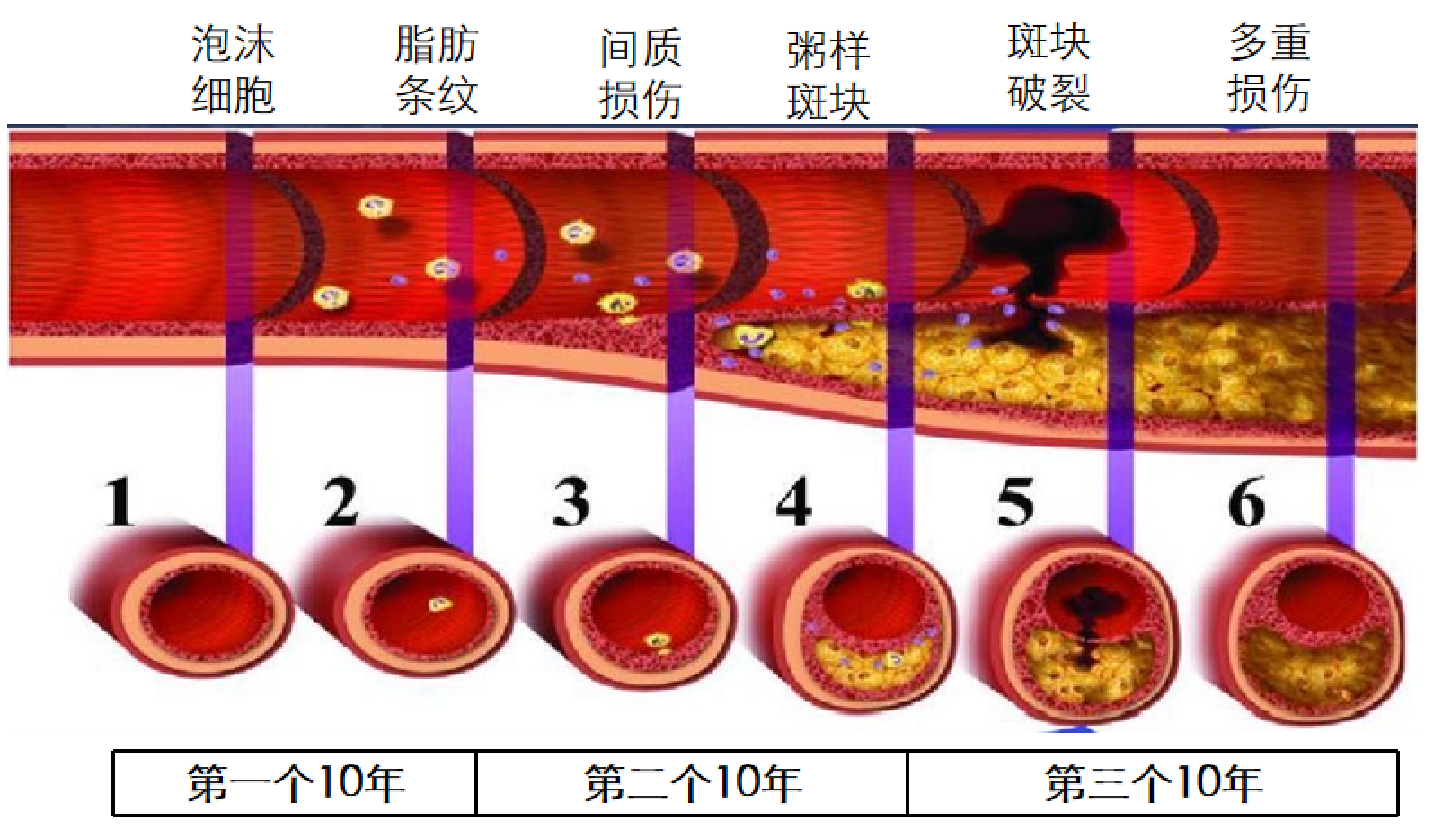

动脉粥样硬化虽然是中老年人的常见病和多发病。但血管粥样硬化的形成并不是一蹴而就的,而是冰冻三尺非一日之寒的结果。现在动脉粥样硬化的发病有年轻化趋势,这当然跟日常的生活方式有关。比如喜吃高热量食品而又不好运动的人,发病率高。同型半胱氨酸是蛋白质中蛋氨酸代谢的中间产物。如果每天摄入蛋白质太多,一时半回儿消化不了,就会导致同型半胱氨酸堆积,导致指标超高(≧10μmol/L)。同型半胱氨酸会激惹动脉血管内皮,造成内皮细胞损伤,引发血管局部炎症,最终导致这段动脉血管壁出现粥样硬化斑块。

从动脉粥样硬化斑块形成开始,到出现明显的症状大约需要20年的时间,再到发生心梗猝死,脑梗偏瘫大约在30年前后。

动脉粥样硬化的发病进程

形成动脉粥样硬化的起始年龄可以非常年轻,可以从青春期的少男少女开始,甚至从孩童期就开始了。